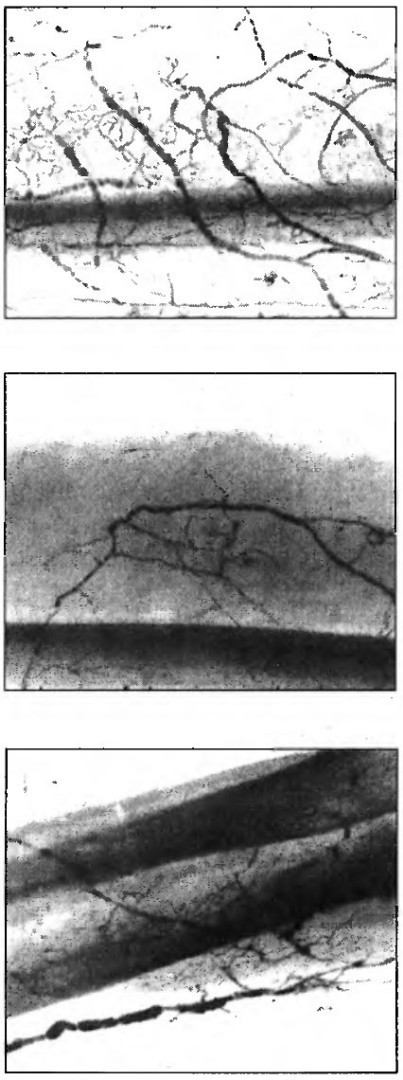

Рентгеновские снимки лимфатических сосудов кожи. Видны сеть мелких сосудов подкожно-жировой клетчатки и крупные собирающие лимфатические сосуды

Реконструкция лимфатических территорий кожи позволила воссоздать пространственную картину групп отводящих сосудов нескольких соседних областей. Оказалось, что самые мелкие сосуды — капилляры — собирают лимфу с обширных областей, затем, как ручейки, впадают в более крупные протоки. В этих более крупных сосудах есть клапаны, ориентирующие ток лимфы в строго заданном направлении — к определенным распределяющим сосудам, которые уже разносят лимфу к лимфатическим узлам. Множественные капилляры объединяются в группу и имеют сток в один отводящий сосуд, который впадает в крупный сосуд между двумя точками его разветвления. В зависимости от длины этого сосуда и определяется лимфатическая зона (сегмент), подчиненная этому сосуду, — если его протяженность до точки разветвления велика, то подчиненная ему зона большая, если точки разветвления расположены близко одна к другой — лимфатическая зона маленькая.